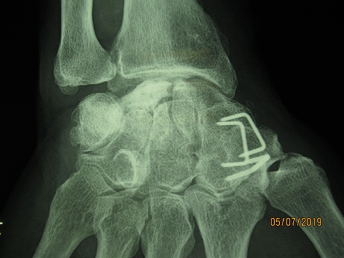

The usual standard treatment is STT arthrodesis. This procedure has been widely tested and there are rarely any complications, and even non-union does not cause pain for a large majority of cases. Figure 5.

In fact, the patient is usually more bothered by the osteosynthesis material and can often ask for it to be removed. This is why my preferred technique is resurfacing the distal pole of scaphoid using an INCA™ prosthesis (Groupe Lepine). The procedure is quick and easy and can be performed through an anterior portal. The outcomes are good, with mild or zero pain and good finger opposition. Figure 6.

The other option is a distal scaphoid excision with tendon interposition (FRC strip), although I tend to use this as a revision solution following failure of a primary INCA arthroplasty. Figure 7.